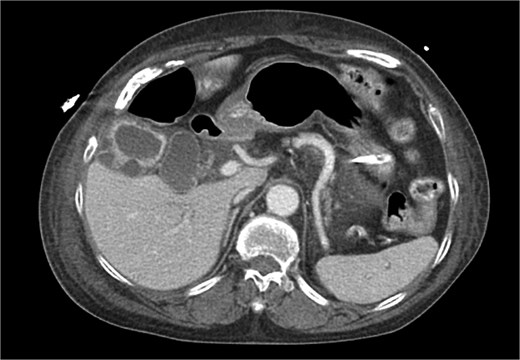

CT chest abdomen pelvis with IV contrast axial view. Gallbladder wall hyperenhancement and multiple intramural hyperattenuating nodes are again apparent in axial imaging.